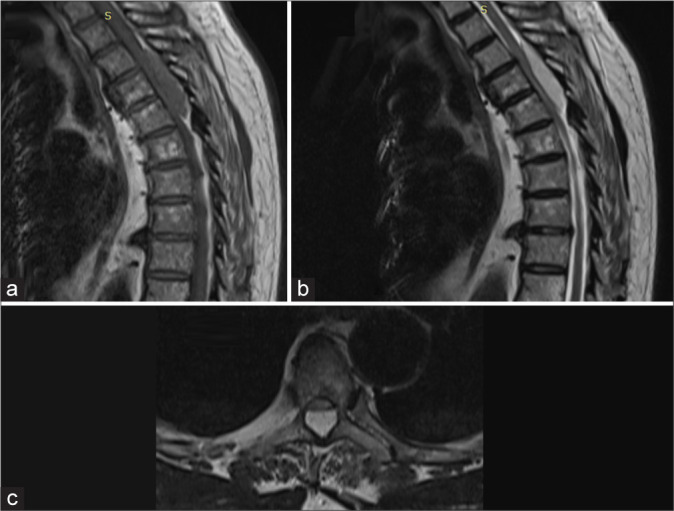

Case description: A 70-year-old male presented with 3 months of progressive paraparesis. The magnetic resonance showed a compressive epidural T3-T5 lesion that was successfully removed. The lesion proved histopathologically to be a benign cavernous angioma.